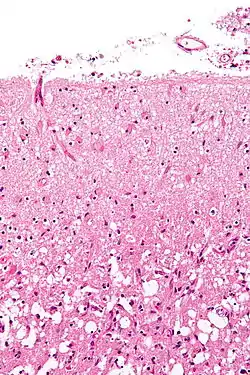

آستروسیتوز (انگلیسی: Astrocytosis) یا آستروگلیوز یا اختریاختگی، به افزایش غیرطبیعی تعداد آستروسیتها به دلیل تباهی یاخته عصبی جانبی، درنتیجهٔ آسیب دستگاه عصبی مرکزی، سکته مغزی، ایسکمی، عفونت، خودایمنی یا بیماریهای نابودکنندهٔ دستگاه عصبی گفته میشود.

![]() شکلگیری اختریاختگی پس از آسیب دستگاه مرکزی عصبی |